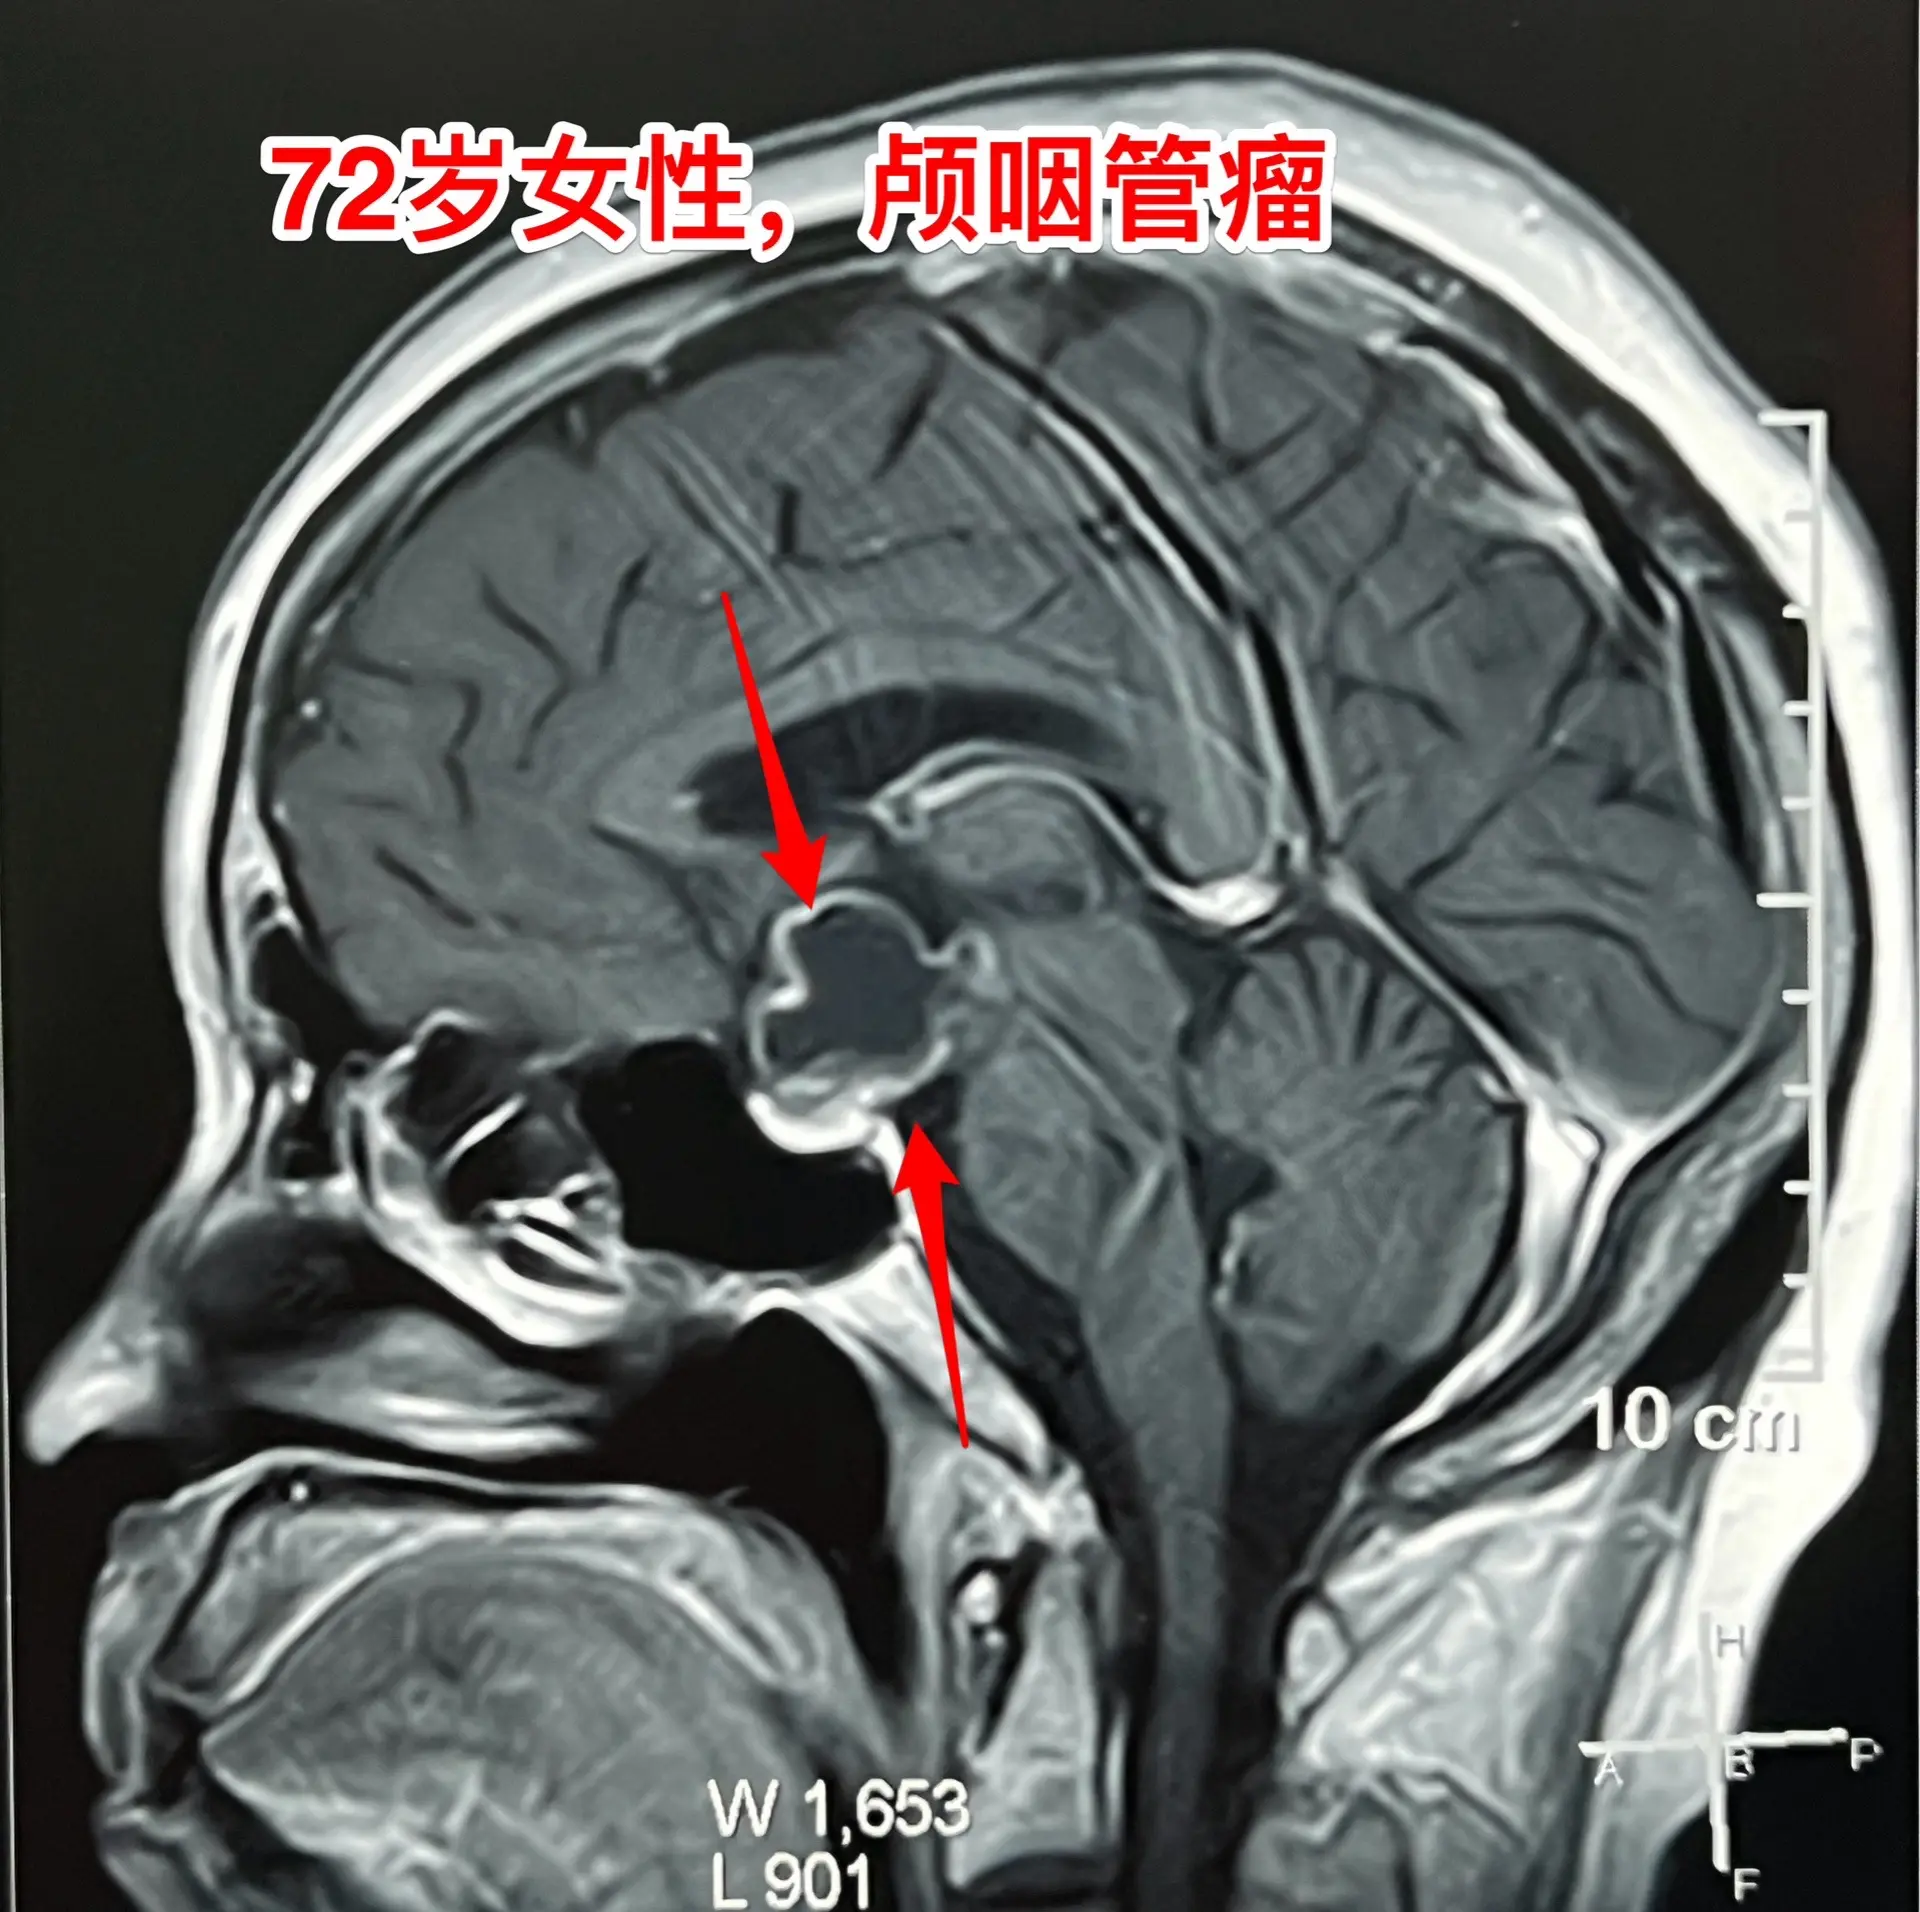

颅咽管瘤不单单是小孩子得的病!很多人认为颅咽管瘤是小孩子得的病,其实各个年龄段的人都可以患颅咽管瘤,我见过的颅咽管瘤病人年龄跨度从不到一岁到八十多岁! 相对而言,小孩子群体中(小于15岁)颅咽管瘤的发生率比较高! 这个72岁的山西晋城市老人在古稀之年患上了颅咽管瘤,病理报告是乳头型颅咽管瘤。10月25日在我科作了手术,11月13日出院。 老人在住院前胃肠功能不好,经常腹胀、消化不良。手术后也是经常感觉腹胀、食欲不振,身体康复过程相对比较缓慢。 老年人一般来说都伴有老年性疾病,比如糖尿病、高血压病、高脂血症、动脉硬化,身体大脏器机能下降,所以老年人患颅咽管瘤,作手术后恢复会比较慢,出意外的风险会增加,尤其是血管方面的并发症会增加,比如深静脉血栓、心肌梗死等。